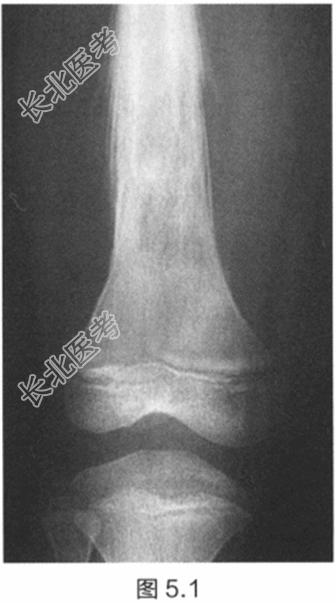

- [材料题] 一名14岁男孩,全科医师发现他股骨中段有明显肿胀。患者还抱怨近几周内自觉疲劳和间歇性发热,导致无法进行少年足球训练。检查:触诊大腿中部,发现一压痛性肿块。推移肿块无活动性。腿部未发现神经或血管受累。初步检查显示白细胞(WBC)、红细胞沉降率(ESR)升高和贫血。股骨X线片如图5.1所示。

- 简答题2、描述X线片所见。